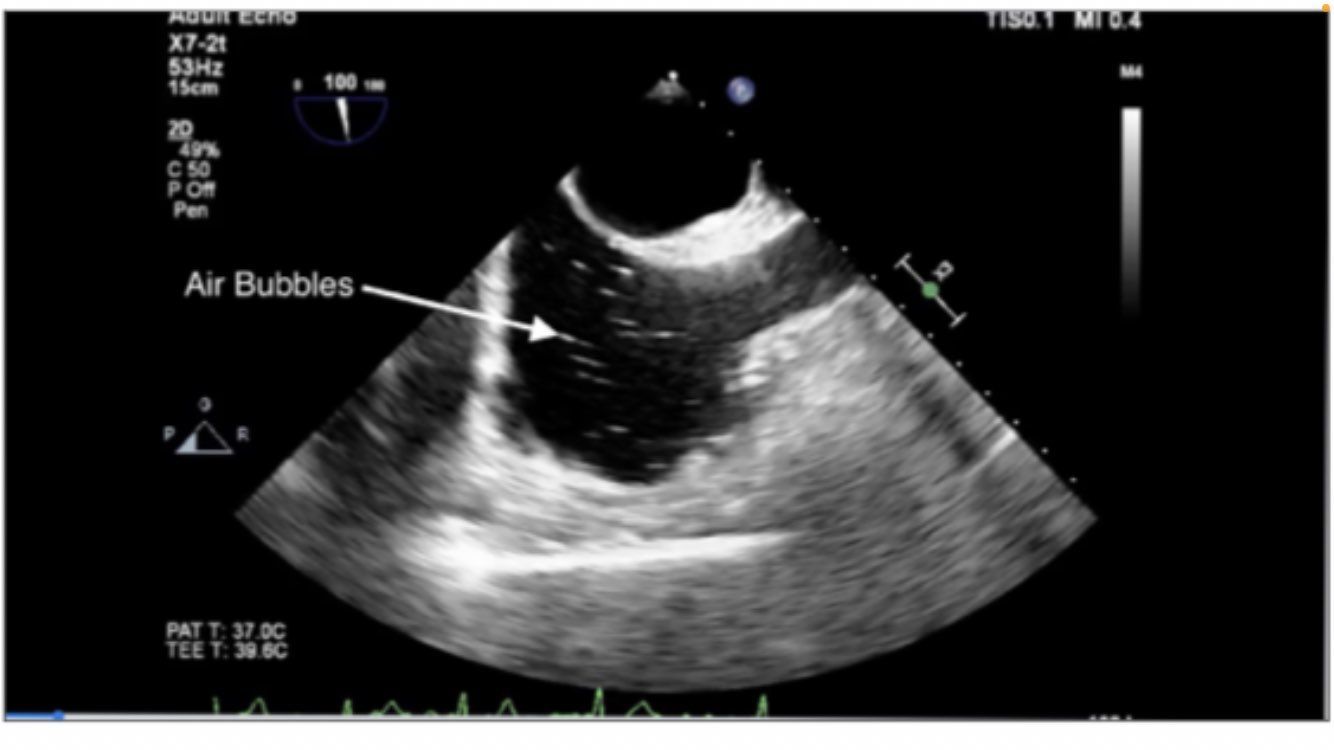

air embolism in right atrium